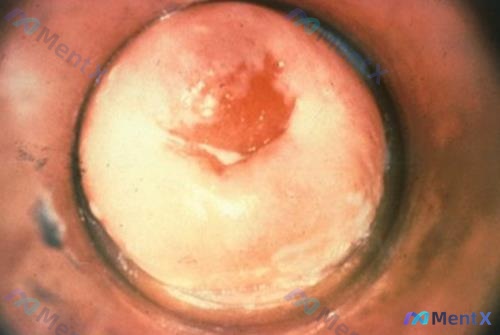

整理到一个病例,第一眼很容易下结论,但仔细想其实藏着一个挺容易踩的坑: 35岁女性,育龄期,查体偶然发现多发子宫肌瘤,同时影像学提示还有多个囊肿。 追问情况:无进行性加重的痛经,也没有月经量多、压迫、不孕这些不适,整体状态很好。 如果只看“多发肌瘤+无症状”,可能直接就定观察了。但这份资料里同时提到...